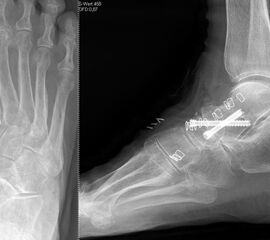

Die isolierte Arthrose der Bona Jäger Gelenkreihe (navikulocuneiforme Gelenk) ist selten und oft posttraumatisch. Meistens geht die navikulocuneiforme Arthrose mit einem schmerzhaften Pes planovalgus einher 2425. Letztlich werden die betroffenen Gelenkflächen angefrischt und mittels verschiedener Implantat-Möglichkeiten (s.o.) fusioniert. Bei gleichzeitiger Plattfußfehlstellung sollte diese ebenfalls adressiert werden 26 (Abb. 4). Ziel ist die Arthrodese in anatomischer Stellung der Gelenke.

Triple-Arthrodese bei einem Pes planovalgus Grad III unter Einschluss des CC-Gelenks.

Abb.10

Die Calcaneocuboidal-Arthrodese ist meistens Teil weiterer Arthrodesen im Bereich der Fußwurzel 34 (Abb. 10).  Eine besondere Bedeutung kommt der Calcaneocuboidal-Arthrodese bei Eingriffen zur Behandlung des Plattfußes, die der Verlängerung der lateralen Säule dienen, zu 35. Die Arthrodese kann mittels Schrauben, Klammern, Plattensystemen und ggf. der Interposition eines kortikospongiösen Spanes zur Verlängerung der lateralen Säule erfolgen.